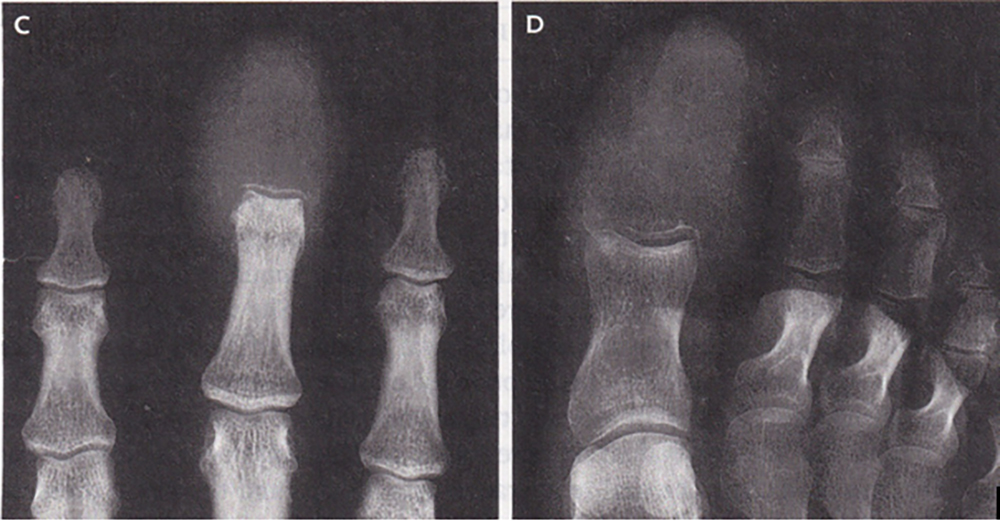

Radiographs (X Rays) of the hands and feet showed destructive lytic lesions that had completely replaced bone in the distal phalanx of the middle finger (Panel C) and great toe (Panel D). A diagnosis of acrometastases was made. Acrometastases are a rare type of bony metastases that are found distal to (outward of) the elbow or knee. Although acrometastases may mimic acute gout, osteomyelitis (bone infection), or a paronychia (ingrown nail), in patients with known cancer plain radiographs aid in making the diagnosis and will help differentiate the correct diagnosis from osteomyelitis, which also destroys bone.